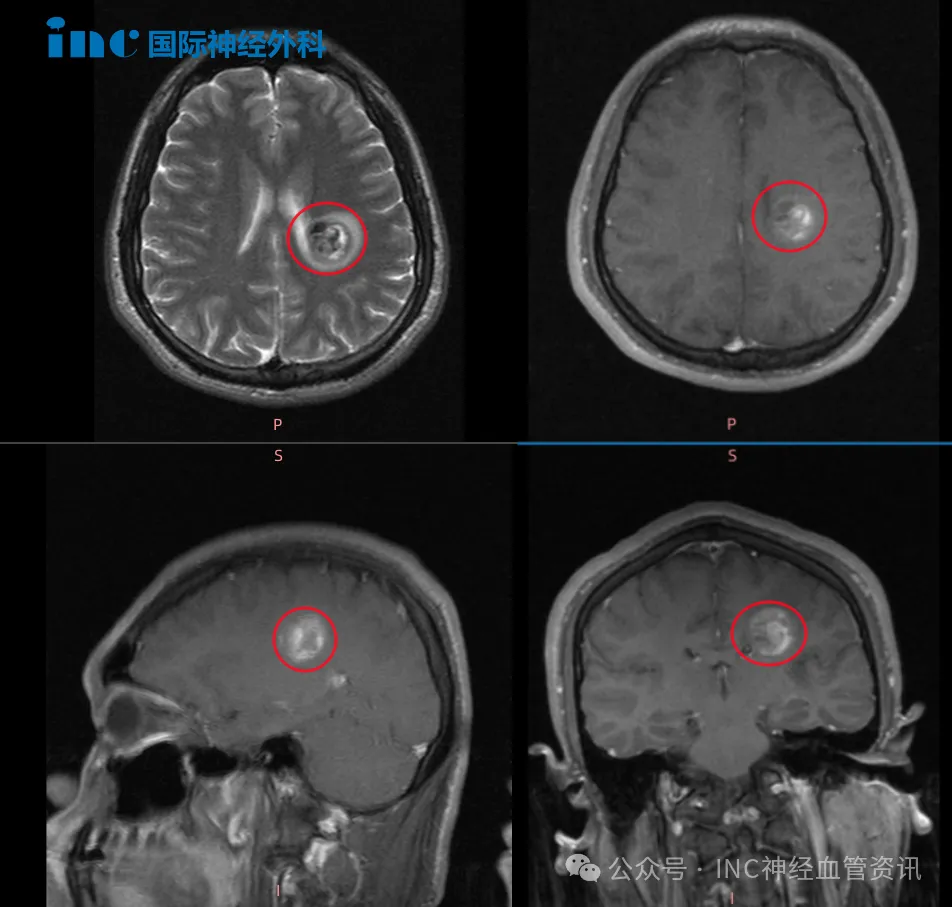

巴教授您好,我现在恢复得还不错! 这句话来自一段丘脑海绵状血管瘤患者文文的恢复视频。镜头里的她行走自如,说话时眉眼带笑,活泼的模样完全看不出三个月前刚经历过一场高难度的脑...